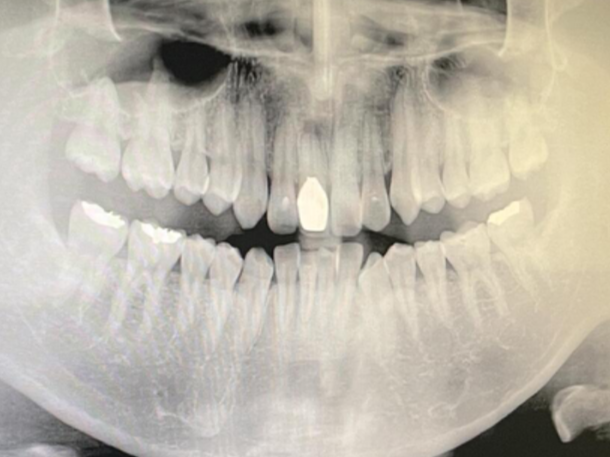

사진 상 하얀 부분은 고등학교 때 축구를 하다가 친구랑 충돌해서 빠졌던 앞니입니다. 그래서 다시 자리를 찾아 꽂아주었고, 치아 윗부분만 신경치료가 되어 있는 상태라고 해요. 처음 알게 된 사실인데, 치아는 원래 잇몸과 약간의 유격을 가지고 있다고 합니다. 그래서 치아를 움직여가며 교정이 가능한 것이라고 합니다. 교정이 끝난 뒤, 교정 보조물을 잘 껴주지 않으면 치아가 원래 상태로 돌아가는 것 역시 이렇게 유격이 있기 때문이라고 해요. 근데 이게 한 번 빠졌다가 다시 고정하기 위해 잇몸에 밀어넣으면, 그 유격이 사라지면서 치아와 잇몸이 붙어버린다고 해요. 그러면 어떻게 되느냐, 이가 움직이지 않는 상황이 되어버리는 것이지요. 돌출된 앞니를 집어넣고 싶던 제 계획이 무너지는 순간이었습니다.